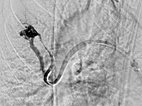

Verschluss der pulmonalen AVM des Oberlappens durch Einbringen von mehreren Platindrahtsprialen (Coils) über den Mikrokatheter unter Schonung der nicht pathologischen Lungenarterien.